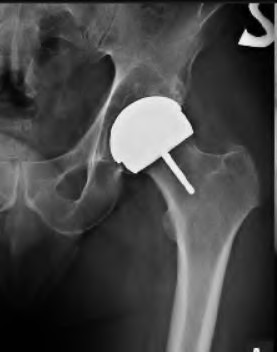

A 72-year-old male presents 2 years status post fixation of an impending pathologic right femur fracture due to metastatic renal cell carcinoma. He is minimally ambulatory due to pain. Despite radiation therapy, there has been progression of the lesion with extensive cortical bone loss, which is shown in Figure A. A proximal femoral replacement arthroplasty is performed without complications, and is demonstrated in Figure B. Which of the following is true regarding this patients post-operative course?

Deep prosthetic infection is the most common complication after hip arthroplasty performed for salvage of failed internal fixation after pathologic proximal femoral fracture secondary to malignancy.

Jacofsky et al reviewed the complications in 42 patients with a mean age of 63 who were treated with hip arthroplasty for salvage of failed treatment of a pathologic proximal femoral fracture. Multiple different constructs were used.

The most common complication was deep prosthetic infection, which occurred in nearly 10% of the patients studied. All infections occured in patients whom had previously received radiation. The mean Harris Hip score improved from 42 to 83 points post-operatively, and 41 of the 42 patients were ambulatory at follow-up. Implant survivorship free of revision for any reason at 5 years was 90%, and free of revision for aseptic failure or radiographic failure was 97%.

Figure A shows a lytic lesion of the proximal femur with an intramedullary implant. Figure B shows a proximal femoral replacement.